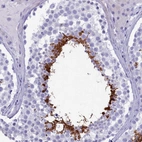

Immunohistochemistry analysis in human testis and kidney tissues using HPA042666 antibody. Corresponding GAPDHS RNA-seq data are presented for the same tissues.